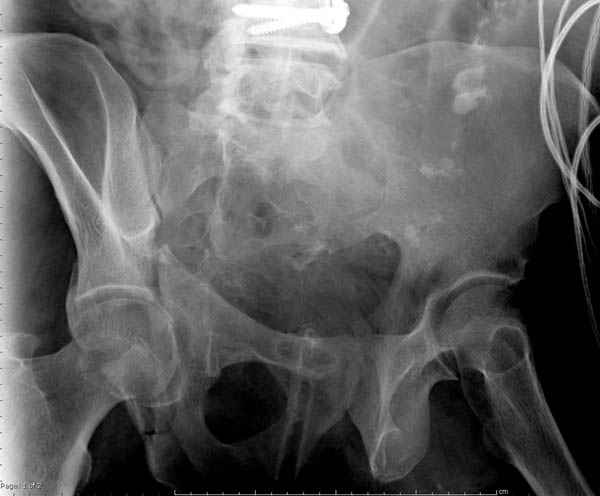

Дополнительно имеется перелом ацетабулума: задняя

колонна с полупоперечным переломом, и переломы костей лица.

На седьмой день зафиксирован перелом ацетабулума через задний доступ. Перед операцией для профилактики DVT, IVC фильтер, также получает Lovenox.

Извиняюсь за качества снимков, обычный больной в 300 фунтов, портативным ренген аппаратом не пробить.

Очень хорошаая работа, поздравляю! Хотелось бы увидеть снимок таза до операции. Каким образом и как долго предполагаете разгружать тазобедреннй сустав в дальнейшшем?

По возможности вышлите снимки, сканы таза до реконструкции, интраоперационные.

По снимку создается впечатление о высоком поперечном переломе, задней колонны, стенки; почему не пользовались *magic screw*?